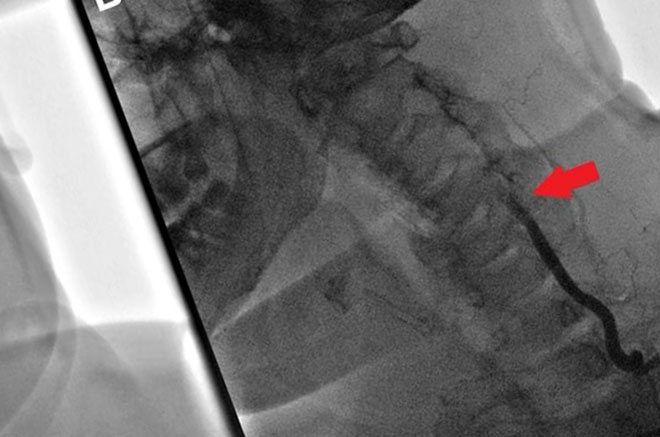

- Ангиография — оценка состояния стенок артерий, метод дает возможность узнать о наличии новообразований.